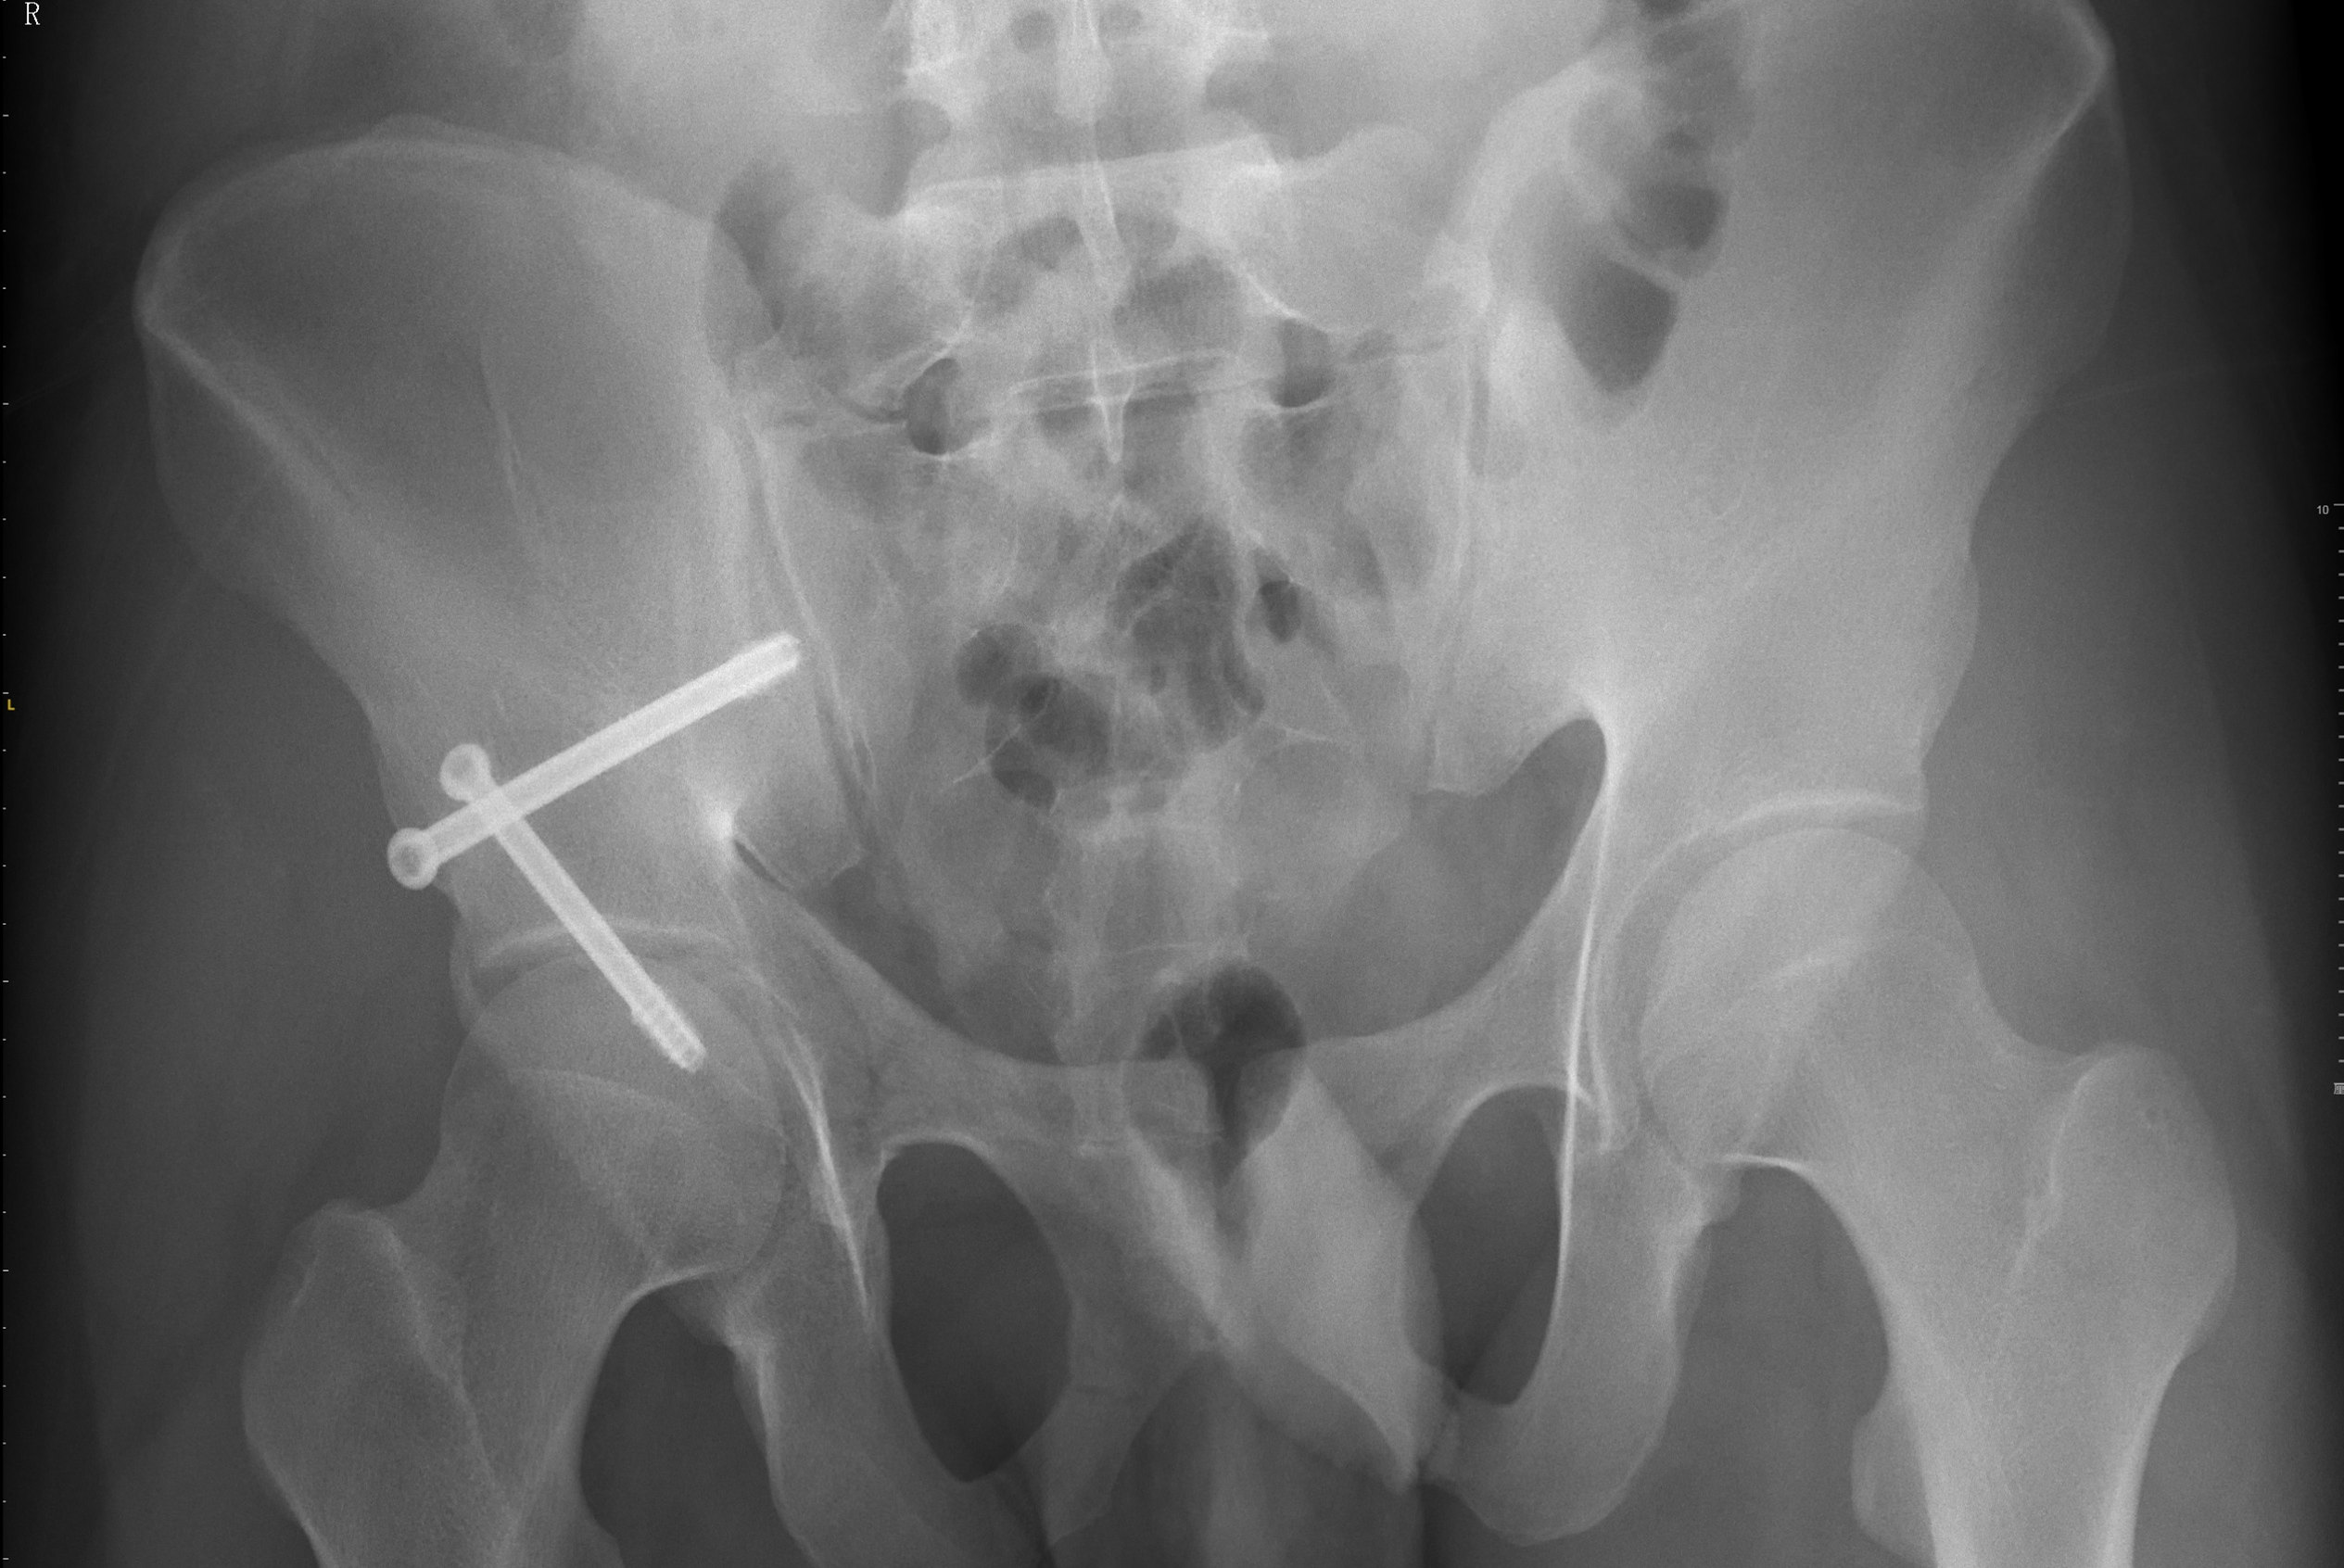

525db6c829e04b8e89913dbfa67466fb.jpg

术后复查的X线片显示骨折复位和固定良好